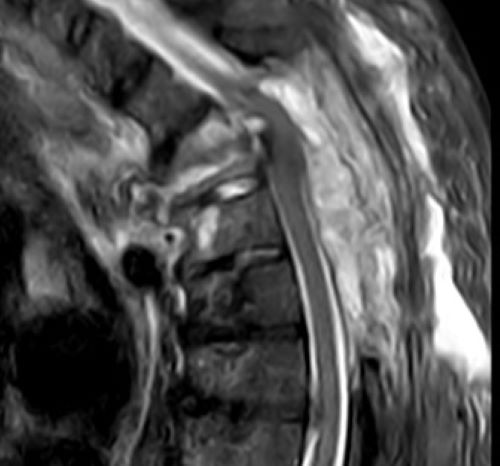

Abbildung zeigt Bilder einer MRT bei Krebs: (1) Wirbelsäulentumor, (2) Knochentumor, (3) Spinalkanaltumor, (4) Mamma-CA (Brustkrebs)

Tumorgewebe ändert die Eigenschaften des betroffenen Gewebes oder wenn es sich um gestreute Tumormetastasen handelt, stellt es sich als Fremdkörpergewebe dar mit anderen Eigenschaften als die Umgebung, die MRT stellt dies technisch als Bildveränderung sichtbar dar und lässt sich somit als Tumor diagnostizieren. Bei zusätzlichen Kontrastmittel-gestützten Bildsequenzen lässt sich zudem das abnormale Durchblutungsverhalten der Tumore erkennen: Das Kontrastmittel ist selbst deutlich als verändertes Signal der Gewebe wahrzunehmen. Tumore können entweder als zeitweise Verstärkung oder Verminderung des Bildsignals im Vergleich zum umgebenden Gewebe abgegrenzt werden.